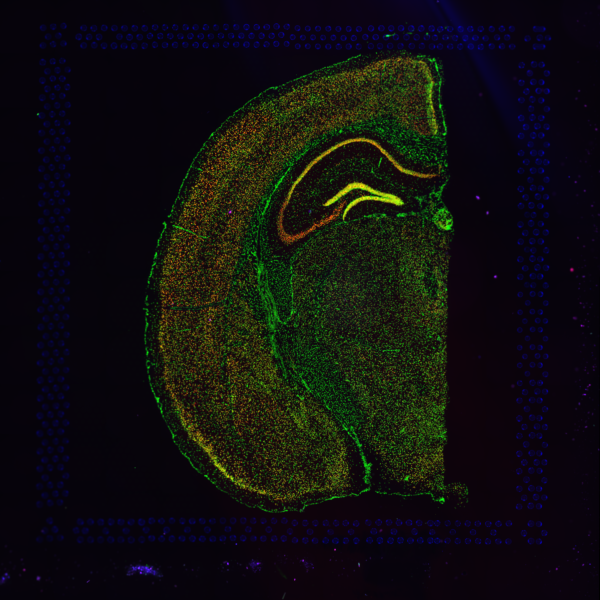

- A fluorescence image comprises one or more grayscale intensity images and is often visualized as a single combined image with a different color assigned to each channel acquired. Each channel corresponds to a different fluorophore that binds to a different protein of interest. Fluorescence microscopy uses excitation with narrow band light and measures a signal emitted from either endogenous or added fluorophores, generating an image with a dark background and a bright foreground. See also the fluorescence imaging demonstrated protocol for Visium.

| Brightfield Image | Fluorescence Image Colorized |

|---|---|

![]() | ![]() |